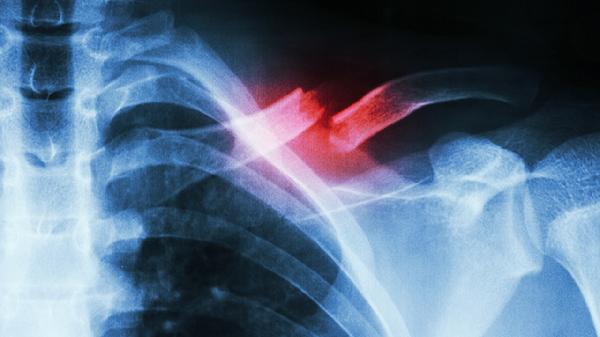

胸膜炎症刺激可导致呼吸时单侧胸痛,可能由肺炎、结核等疾病继发。听诊可闻及胸膜摩擦音,CT检查可明确诊断。治疗原发病的同时,可配合使用阿司匹林肠溶片缓解疼痛,结核性胸膜炎需规范抗结核治疗。建议保持半卧位减轻呼吸牵拉痛。